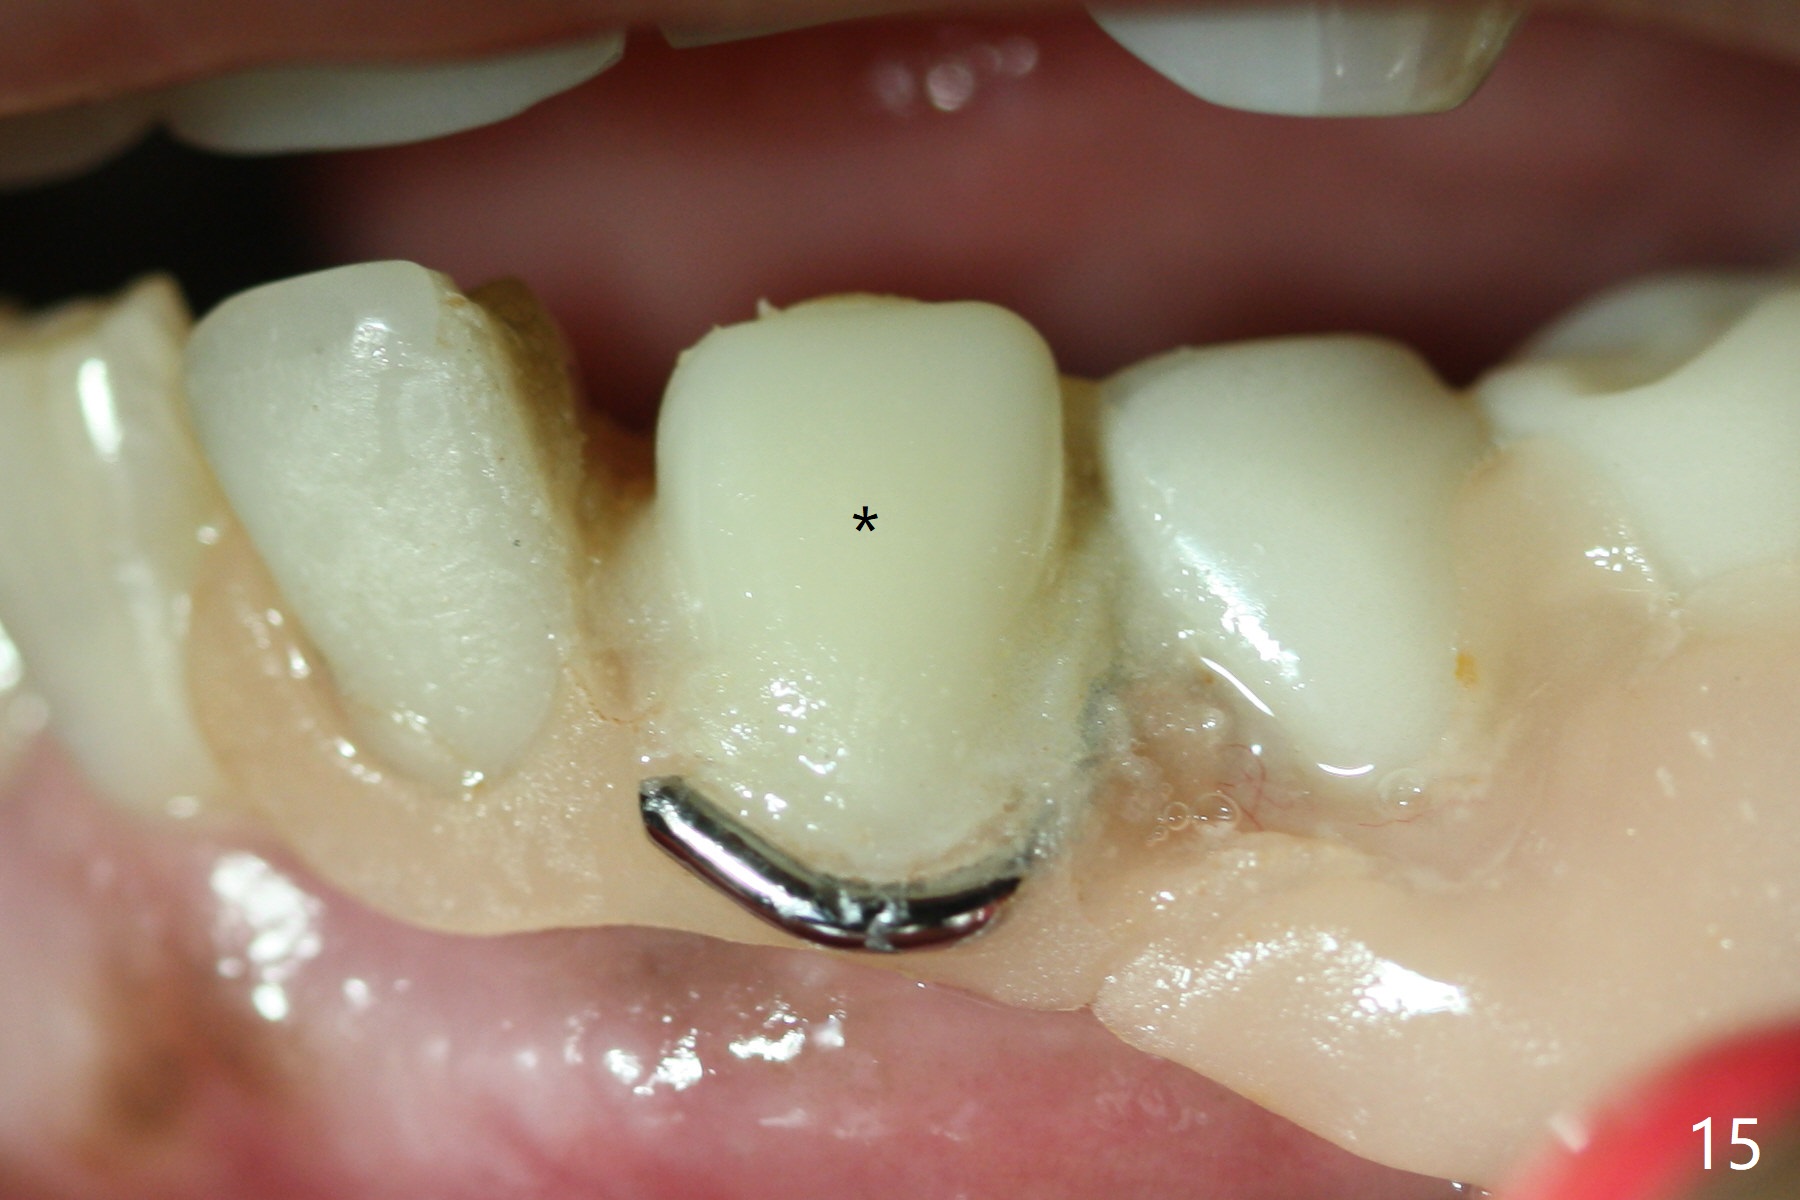

The inflammation around the tooth #22 (Fig.1 *) and mobility may be related to trauma from the only clasp of the lower flipper (Fig.2). The latter is loose with space underneath (>) and laterally (Fig.3 *). The distobuccal plate is defective upon extraction; the osteotomy is initiated in the mesiolingual slope of the socket (Fig.4) with ~ 6 mm native bone. When a 3.8x15 mm dummy implant achieves insertion torque of 50 Ncm, the insertion is incomplete with apical space (Fig.5 *). The definitive implant (3.8x13 mm) closes the apical space and obtains insertion torque >55 Ncm; a ball abutment with 2 mm cuff seems to be short for retention (Fig.6). A 4.5x4(5) mm cemented abutment (Fig.7,8) seems appropriate for retention after soft reline of the lower flipper (Fig.9-11). The socket heals without bone graft exposure 8 days postop (Fig.12,13). To satisfy the patient's desire to have a white tooth, the buccal portion of the soft reline and the abutment is removed (Fig.14) and a crown form is added (Fig.15 *). The socket obliterates 3 months postop (Fig.16).